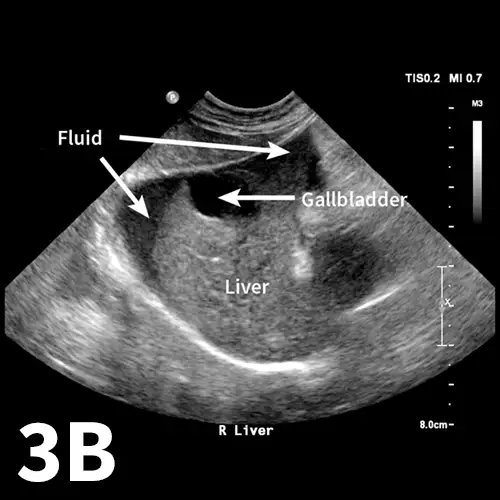

More than 10 years ago, a novel ultrasound protocol, abdominal focused assessment with sonography for trauma (aFAST), was described in veterinary literature1 and has changed the way emergency patients are evaluated for intraabdominal trauma. One of the most common signs of abdominal trauma is detection of free fluid within the peritoneal space. Most frequently, this fluid is a result of hemorrhage from blunt force trauma to the spleen or liver, although rupture of the urinary bladder or gallbladder is also a source of abdominal fluid in emergency patients. Before the widespread use of ultrasonography, blind abdominocentesis and radiography were the most readily available techniques to assess patients for peritoneal fluid. However, radiography has been shown to be less sensitive than ultrasonography, with ultrasonography experimentally being up to twice as sensitive as radiography with relatively small amounts of fluid (up to 2 mL/lb).2

The aFAST examination divides the abdomen into 4 quadrants. A good way to perform the examination is to use a clock-face analogy and begin at the 12-o’clock position (Clock-face). The starting position, designated the diaphragmatic–hepatic (DH) position, is caudal to the xiphoid process; it is useful for finding fluid between liver lobes and the diaphragm. The next quadrant lies at the 3-o’clock position over the left flank and is designated the spleno–renal (SR) position. Both the spleen and left kidney should be visible within this region. At the 6-o’clock position over the caudal abdomen, the urinary bladder and colon can be seen, making this window the cysto–colic (CC) position. The final quadrant within the aFAST examination is over the right flank at the 9-o’clock position, designated the hepato–renal (HR) position. The right kidney and liver should be visible within this region.1,4

Applying the abdominal fluid scoring (AFS) system when evaluating each quadrant of the abdomen during the aFAST examination may be useful. The AFS is a 4-point scale that starts at 0 (negative for peritoneal fluid). One point is assigned for each quadrant in which fluid is identified, up to 4 points total. The amount of fluid in a particular quadrant does not affect the score (ie, any amount of fluid, minimal-to-severe, receives the same point value of 1). It is important to note that AFS scores are only validated in dogs when the examination is performed with the patient in right lateral recumbency. Dogs with AFS scores of 3 and 4 are more likely to require blood transfusions compared with dogs with AFS scores of 0 to 2.4

As with many skills in veterinary medicine, becoming proficient at the aFAST examination and maneuvering the ultrasound probe requires practice. The aFAST examination can be easy to learn and a good way to identify peritoneal fluid in patients with recent motor vehicle trauma. The aFAST examination also has applications in patients that present with an acute abdomen but no known trauma. With gained proficiency, clinicians may be able to diagnose other conditions (eg, splenic mass, gallbladder mucocele) that could require acute intervention.